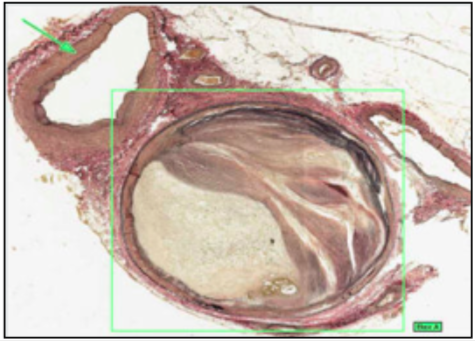

ARTERY WITH PLAQUE AND THROMBUS (WITH IRON HAEMATOXYLIN)

- elastic/nucleus = black